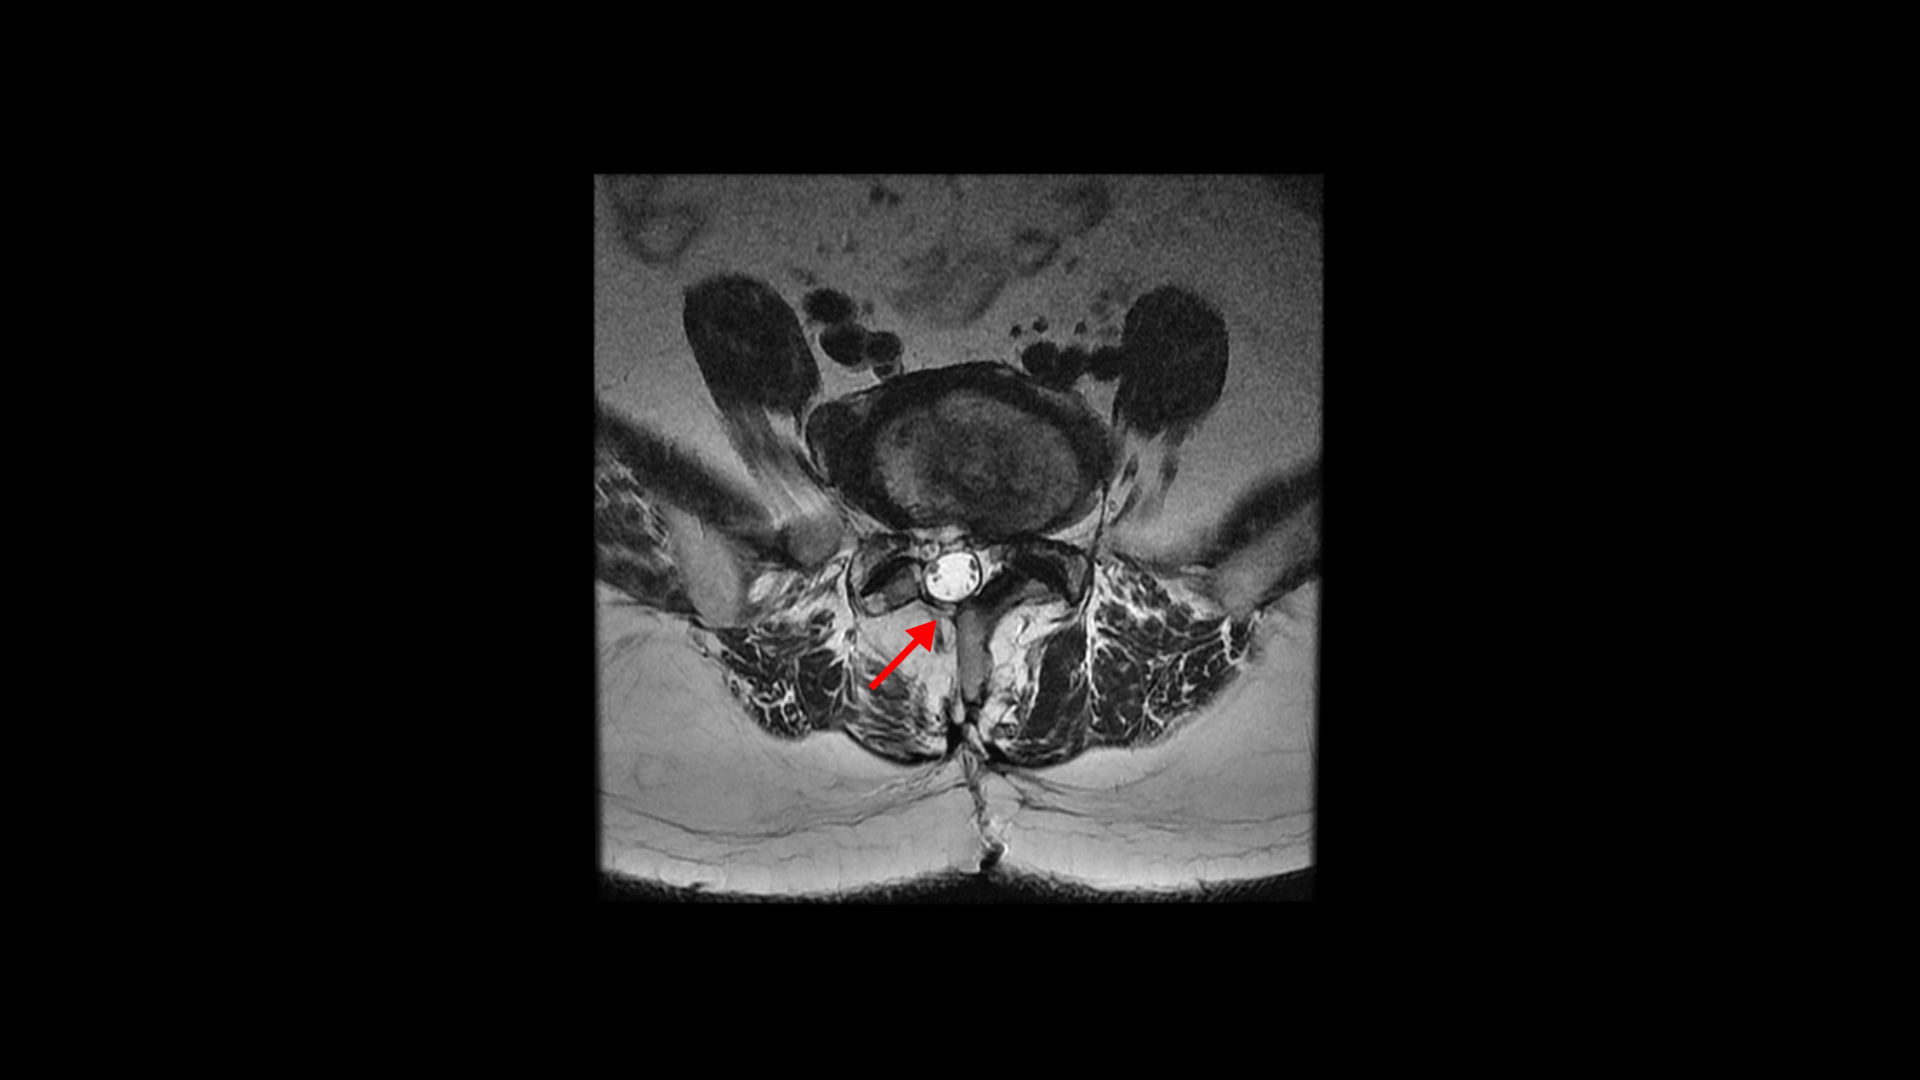

이 환자분은 허리수술을 여러 번 한 상태에서 결국에는 척추유합술까지 하셨습니다. MRI를 보시면 5번 1번 후궁에 수술한 자국이 보입니다.

올해 초에 4번 5번 디스크가 또 오른쪽으로 심하게 파열돼서 결국 후궁과 후관절, 황색인대를 모두 다 제거하고 나사를 박는 척추유합술을 하셨습니다.